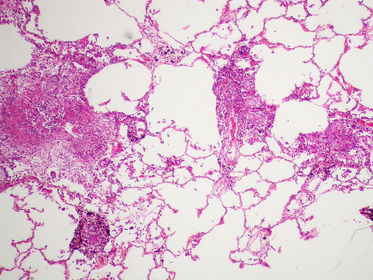

TISSUE TYPE: dots on white page :D... white page= alveolar spaces.. u can see carbon particles (anthracosis)..LUNG PATHOLOGY: inflamatory cells in alveolar spaces .. DIAGNOSIS: acute lobar pneumonia KEY: WHITE BACKGROUND ..